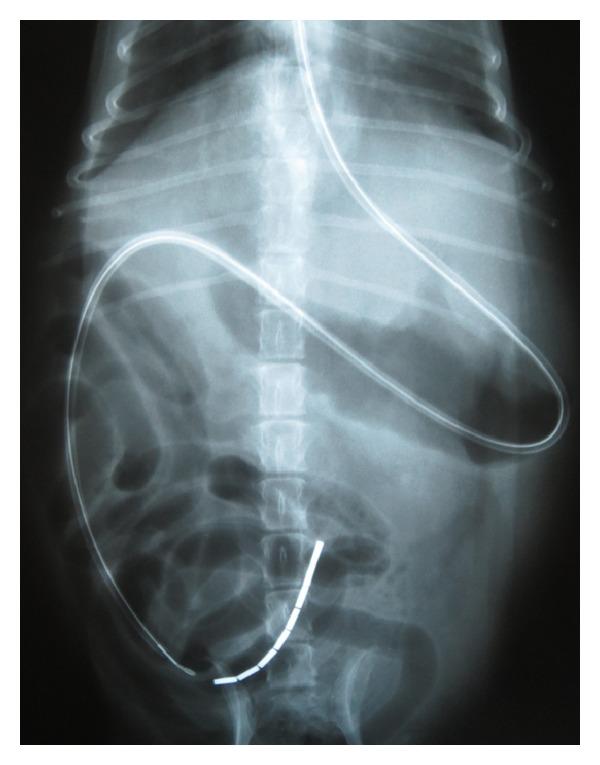

Enteral feeding tube placement has been described in veterinary medicine for several years. Indications include oral, esophageal, gastrointestinal, pancreatic, hepatic, and neurologic diseases. In this paper, endoscopically assisted placement of an esophagojejunostomy (EJ) feeding tube in dogs with pancreatitis and prolonged anorexia is described. To the author's knowledge there are no published reports of this procedure. Esophagojejunostomy feeding tubes provide an alternative to other forms of postgastric feeding tube placement (e.g., nasojejunal, gastrojejunostomy, and jejunostomy tubes) without the associated complications of patient discomfort, sneezing, epistaxis, and peritonitis. Tube occlusion, transient vomiting and loose stool were the most commonly reported complications.

肠内饲管放置在兽医学中已有数年历史。适应证包括口腔、食管、胃肠道、胰腺、肝脏和神经系统疾病。本文描述了在患有胰腺炎和长期厌食症的犬中,通过内镜辅助放置食管空肠造口术(EJ)饲管的方法。据作者所知,尚无关于该手术的发表报告。食管空肠造口术饲管为胃后饲管放置的其他形式(如鼻空肠管、胃空肠造口术管和空肠造口术管)提供了一种替代方法,且没有患者不适、打喷嚏、鼻出血和腹膜炎等相关并发症。饲管堵塞、短暂呕吐和稀便是最常报告的并发症。